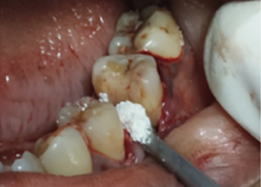

Post-OP Clinical View

Bone Graft Placement

Placement of PRF Membrane